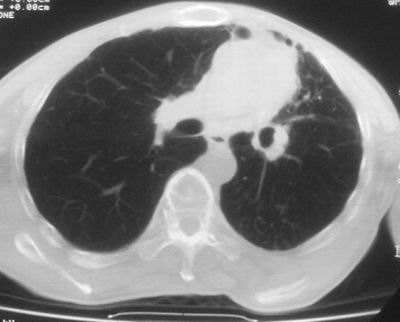

标题: CT11864:男,47岁,反复咳嗽、咯痰、咯血3年,请分析. [打印本页]

患者,男,47岁,反复咳嗽、咯痰、咯血3年,再发5天。痰培养未找到真菌、抗酸杆菌、癌细胞。

左肺上叶体积明显缩小,其内见多发透光区,纵隔向左侧移位,左肺下叶多发班片状病灶,边界模糊,1左肺上叶先天肺发育不全,2左肺下叶肺炎,

左肺上叶结核伴肺纤维化,纵隔移位,左肺下叶感染性病变,建议抗炎抗结核后复查,双肺气肿.

考虑:左肺慢纤伴霉菌球形成、双肺全小叶型肺气肿。

1)考虑为:左肺上叶肺结核(空洞形成),伴左下肺感染;不排除霉菌感染可能。2)肺气肿。

左肺上叶结核伴肺纤维化空洞形成并左肺下叶感染,纵隔牵拉移位,建议作进一步检查排除左侧肺霉菌感染可能。